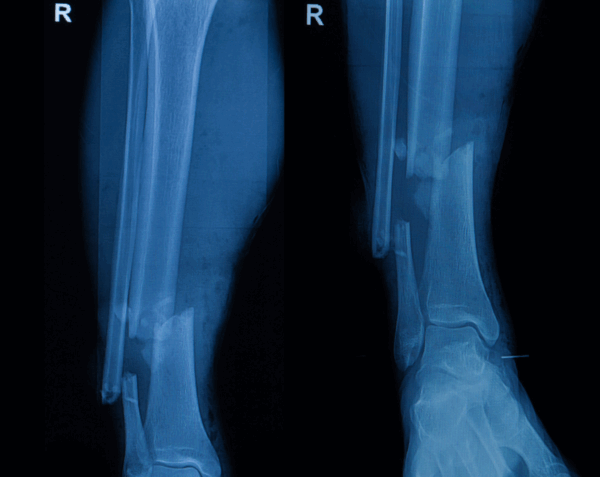

Mobile Right Tib/Fib X-Ray AH (After Hours) in Phoenix Metro

Precision Imaging for Lower Leg Pain and Injuries

A right tib/fib X-ray provides detailed images of the tibia (shinbone) and fibula (the slender bone alongside it). Physicians often order this study to evaluate fractures, infections, bone alignment, or post-surgical healing. At Desert Mobile Medical, we bring hospital-grade mobile X-ray technology directly to you—so you receive fast, accurate results without the hassle of urgent care visits or hospital delays.

When a Right Tib/Fib X-Ray AH is Needed

Injury or Trauma – To identify fractures after falls, accidents, or sports injuries.